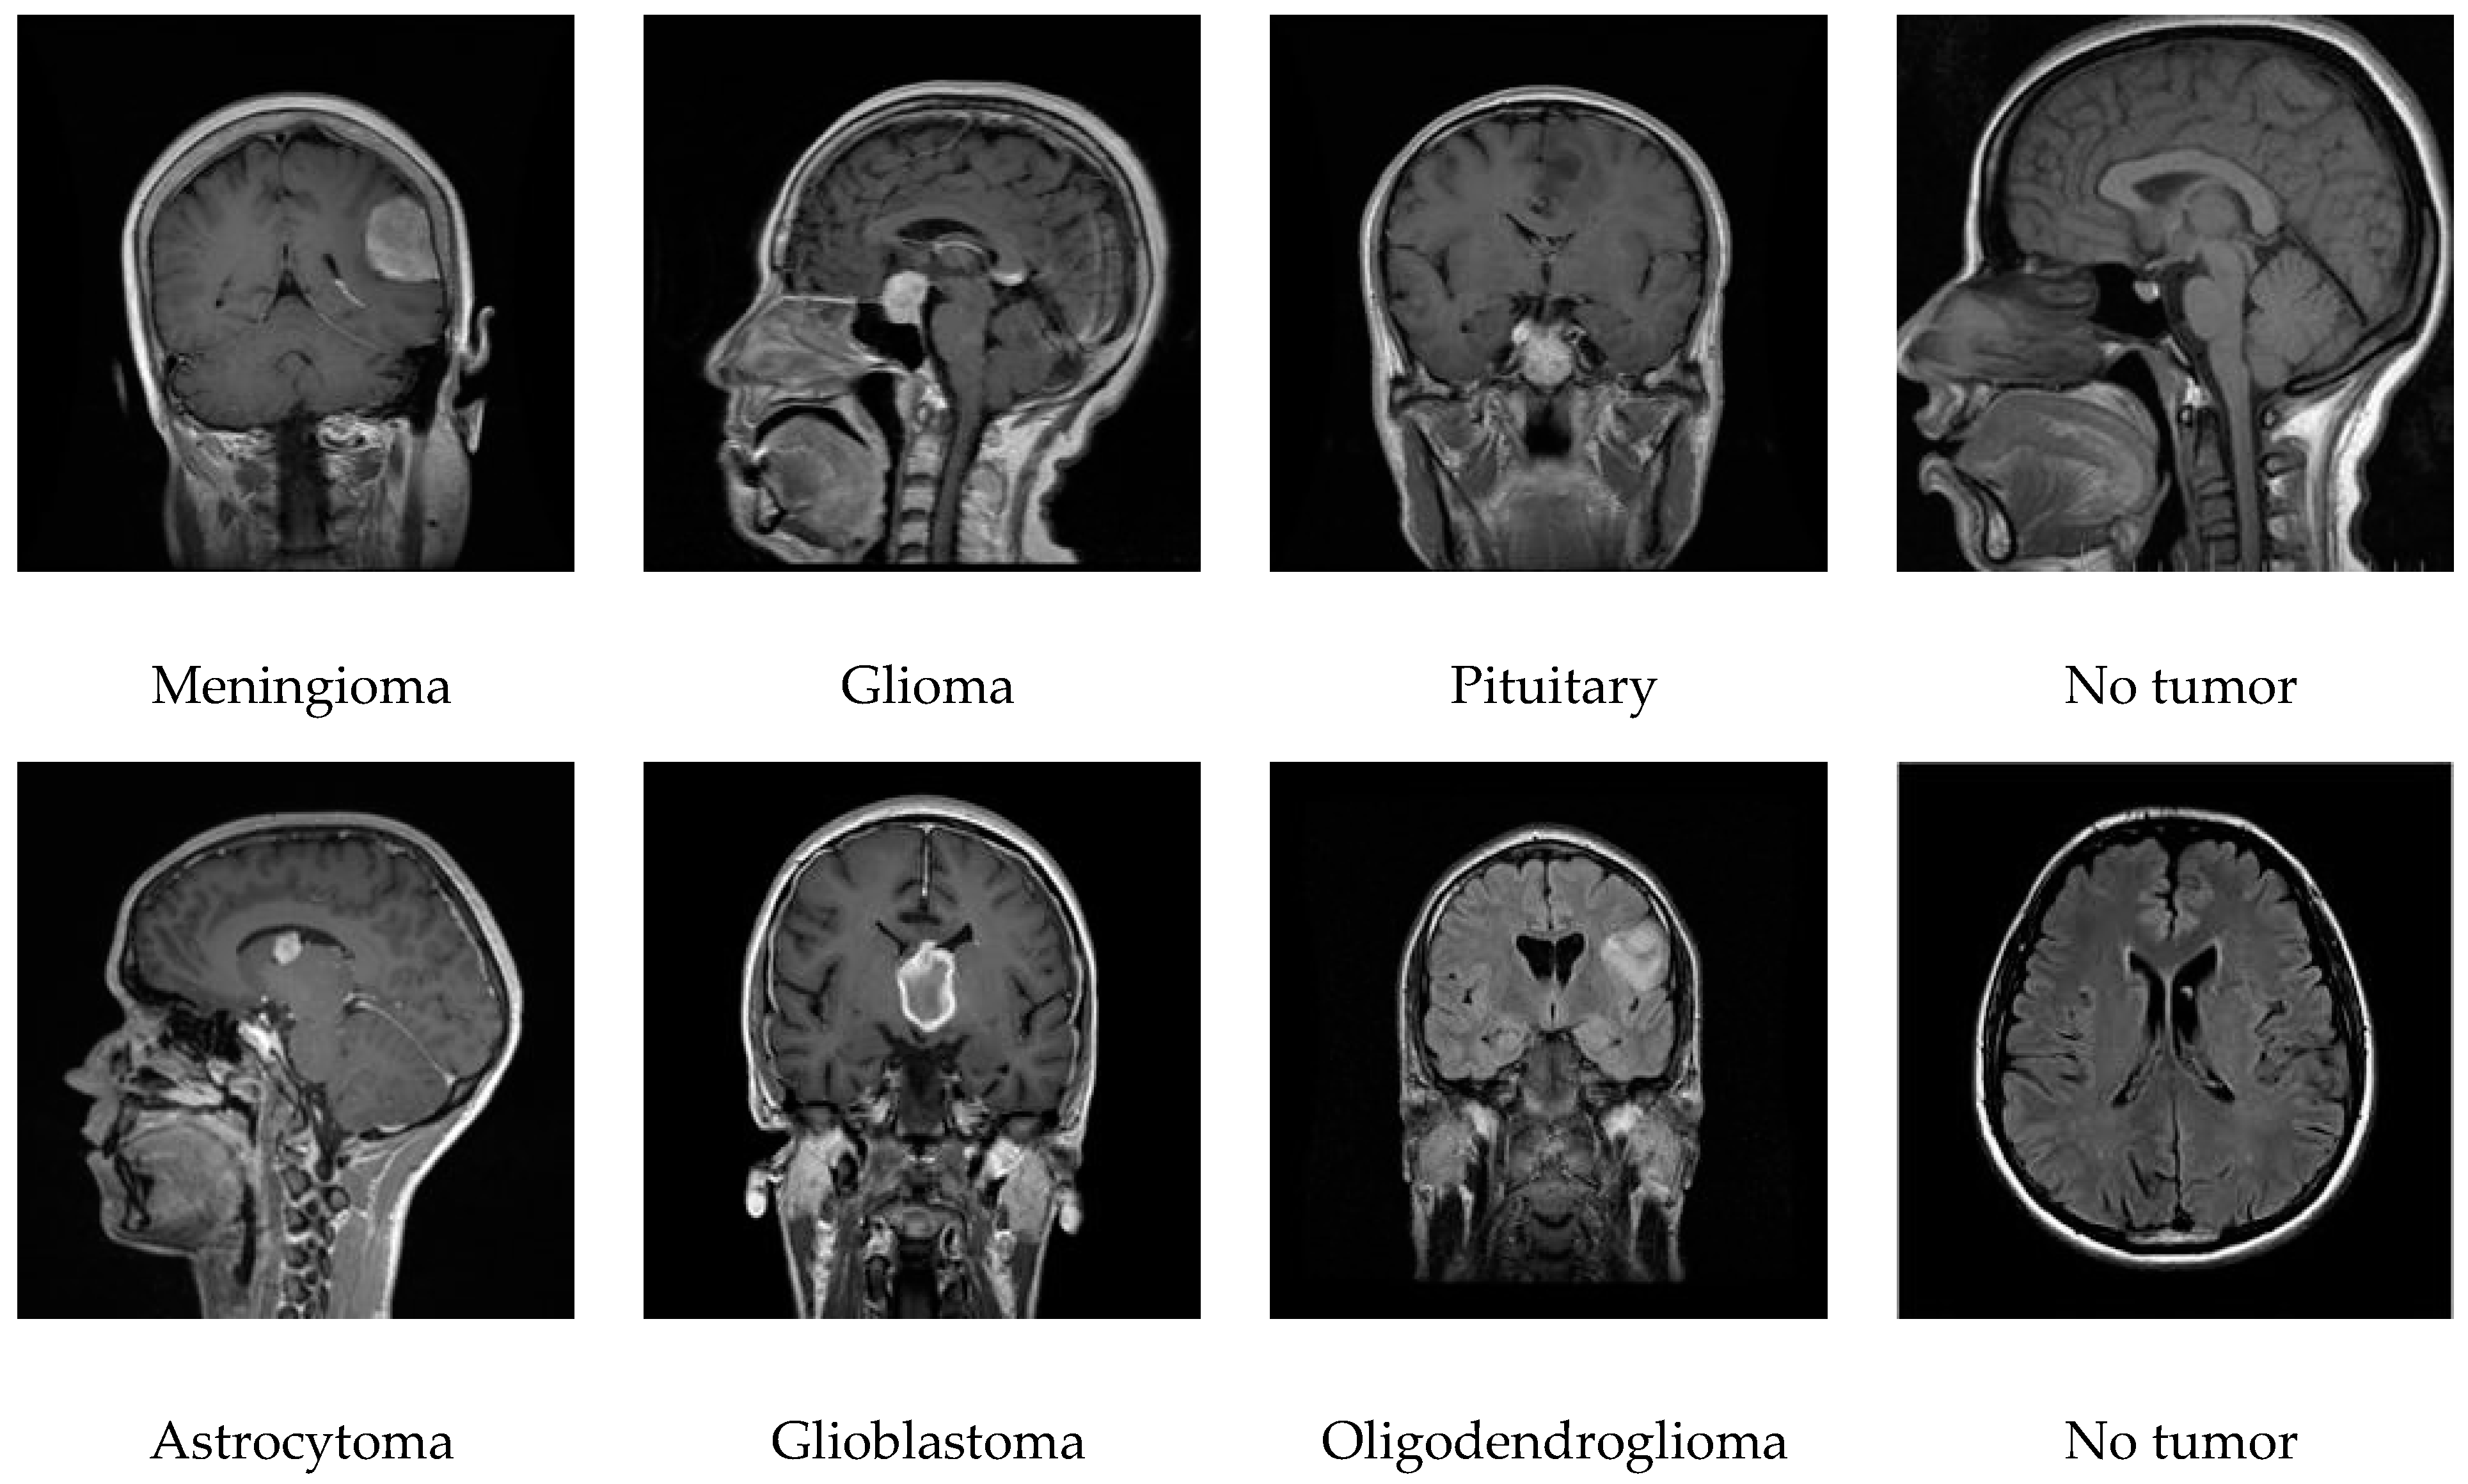

3.2. Datasets

| Tumor Types | Dataset Details/Specs for Seven Classes | Dataset Details/Specs for Four Classes | ||

|---|---|---|---|---|

| Dataset Source 1 | Dataset Source 2 | Dataset Source 1 | Dataset Source 2 | |

| Glioma | 826 | 300 | 826 | 300 |

| Meningioma | 822 | 306 | 822 | 306 |

| Pituitary | 827 | 300 | 827 | 300 |

| No tumor | 395 | 405 | 395 | 405 |

| Glioblastoma | 165 | 20 | --- | --- |

| Astrocytoma | 57 | 15 | --- | --- |

| Oligodendroglioma | 45 | 19 | --- | --- |

| Total | 3137 | 1365 | 2870 | 1311 |